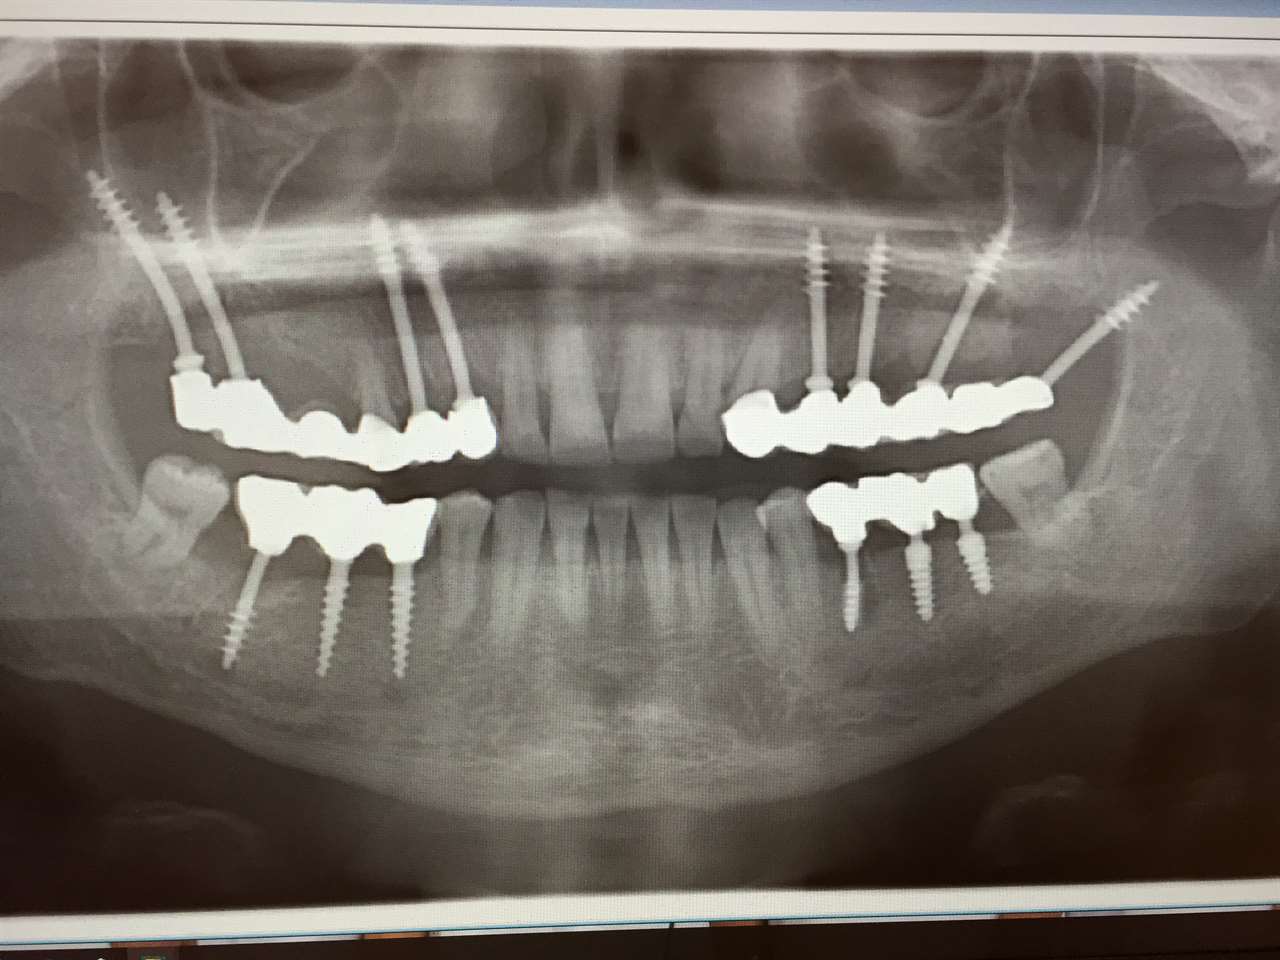

Teljes alsó,felső állcsont helyreállítása azonnal

terhelhető implantátumokkal és porcelán hidakkal.